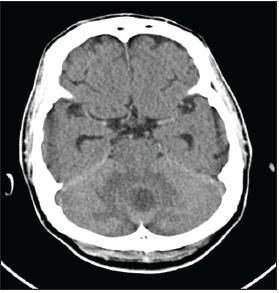

ACT scan of the head revealed a cerebellar vermian mass of 1.8 cm with associated vasogenic edema and moderate cerebral atrophy (Figure 1). An MRI scan of the brain revealed 2 predominant ring-enhancing lesions with surrounding vasogenic edema (Figure 2).

Figure 1 -

This CT scan of thehead, taken on admission,shows a cerebellar vermianmass with associatedvasogenic edema andmoderate cerebral atrophy.